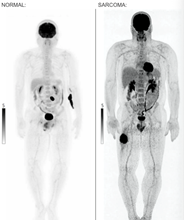

Thigh Sarcoma AI

Thigh Sarcoma Detection

Automatic detection on whole body PET/CT.